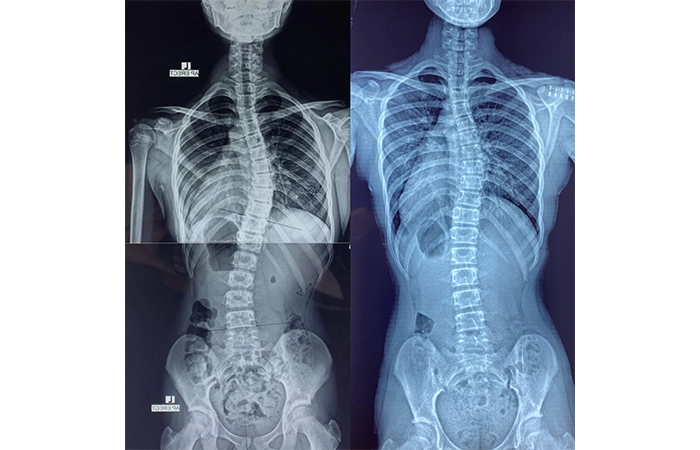

脊柱側彎是指脊骨向左或向右彎曲至呈現「C」形或「S」形,超過十度或以上。大部分脊柱側彎的成因不明,而且通常在青春期十至十五歲出現,女性為多,我們稱之為「青少年原發性脊柱側彎」。脊椎側彎常見的特徵有高、低膊,腰部大細邊,盆骨左右不對稱或長短腳等。 另外亦有成人退化性脊柱側彎。